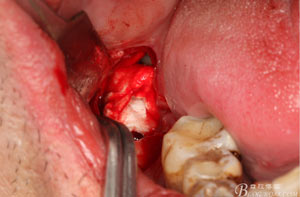

圖12. 先取出48牙冠

圖13.從頰側(cè)和舌側(cè)兩個(gè)方向用挺。挺出牙根